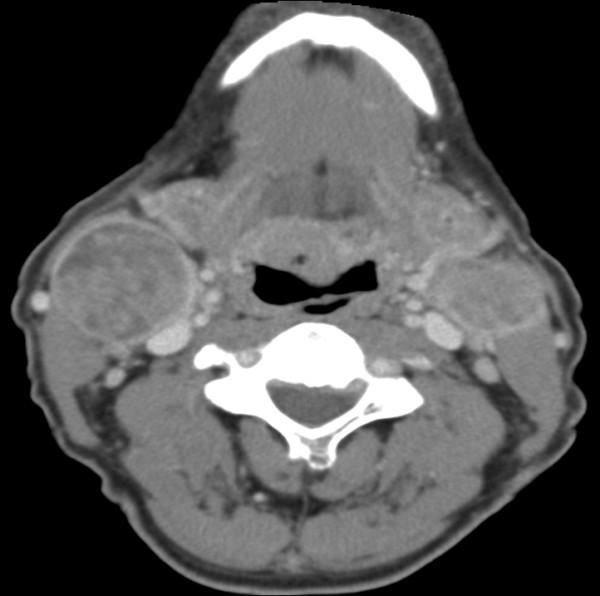

115例T1-T2期口腔鳞状细胞癌患者的临床病理参数、复发情况、局部区域及远处转移情况

Clinicopathological parameters, recurrence, locoregional and distant metastasis in 115 T1-T2 oral squamous cell carcinoma patients.

The incidence of oral squamous cell carcinoma remains high. Oral and oro-pharyngeal carcinomas are the sixth most common cancer in the world. Several clinicopathological parameters have been implicated in prognosis, recurrence and survival, following oral squamous cell carcinoma. In this retrospective analysis, clinicopathological parameters of 115 T1/T2 OSCC were studied and compared to recurrence and death from tumour-related causes. The study protocol was approved by the Joint UCL/UCLH committees of the ethics for human research. The patients' data was entered onto proformas, which were validated and checked by interval sampling. The fields included a range of clinical, operative and histopathological variables related to the status of the surgical margins. Data collection also included recurrence, cause of death, date of death and last clinic review. Causes of death were collated in 4 categories (1) death from locoregional spread, (2) death from distant metastasis, (3) death from bronchopulmonary pneumonia, and (4) death from any non-tumour event that lead to cardiorespiratory failure. The patients' population comprised 65 males and 50 females. Their mean age at the 1st diagnosis of OSCC was 61.7 years. Two-thirds of the patients were Caucasians. Primary sites were mainly identified in the tongue, floor of mouth (FOM), buccal mucosa and alveolus. Most of the identified OSCCs were low-risk (T1N0 and T2N0). All patients underwent primary resection +/- neck dissection and reconstruction when necessary. Twenty-two patients needed adjuvant radiotherapy. Pathological analysis revealed that half of the patients had moderately differentiated OSCC. pTNM slightly differed from the cTNM and showed that 70.4% of the patients had low-risk OSCC. Tumour clearance was ultimately achieved in 107 patients. Follow-up resulted in a 3-year survival of 74.8% and a 5-year survival of 72.2%. Recurrence was identified in 23 males and 20 females. The mean age of 1st diagnosis of the recurrence group was 59.53 years. Most common oral sites included the lateral border of tongue and floor of mouth. Recurrence was associated with clinical N-stage disease. The surgical margins in this group was evaluated and found that 17 had non-cohesive invasion, 30 had dysplasia at margin, 21 had vascular invasion, 9 had nerve invasion and 3 had bony invasion. Severe dysplasia was present in 37 patients. Tumour clearance was achieved in only 8 patients. The mean depth of tumour invasion in the recurrence group was 7.6 mm.An interesting finding was that 5/11 patients who died of distant metastasis had their primary disease in the tongue. Nodal disease comparison showed that 8/10 patients who died of locoregional metastasis and 8/11 patients who died from distant metastasis had clinical nodal involvement. Comparing this to pathological nodal disease (pTNM) showed that 10/10 patients and 10/11 patients who died from locoregional and distant metastasis, respectively, had nodal disease. All patients who died from locoregional and distant metastasis were shown to have recurrence after the primary tumour resection. Squamous cell carcinoma of the oral cavity has a poor overall prognosis with a high tendency to recur at the primary site and extend to involve the cervical lymph nodes. Several clinicopathological parameters can be employed to assess outcome, recurrence and overall survival.

口腔鳞状细胞癌的发病率仍然很高。口腔癌和口咽癌是全球第六大常见癌症。口腔鳞状细胞癌发生后,一些临床病理参数与预后、复发和生存率相关。在这项回顾性分析中,研究了115例T1/T2期口腔鳞状细胞癌的临床病理参数,并将其与肿瘤相关原因导致的复发和死亡情况进行比较。该研究方案已获得伦敦大学学院/大学学院医院人类研究伦理联合委员会的批准。患者数据被录入表格,并通过间隔抽样进行验证和检查。这些领域包括一系列与手术切缘状态相关的临床、手术和组织病理学变量。数据收集还包括复发情况、死亡原因、死亡日期和最后一次临床复查。死亡原因分为4类:(1) 局部区域扩散导致的死亡;(2) 远处转移导致的死亡;(3) 支气管肺炎导致的死亡;(4) 任何导致心肺功能衰竭的非肿瘤事件导致的死亡。患者群体包括65名男性和50名女性。他们首次诊断为口腔鳞状细胞癌时的平均年龄为61.7岁。三分之二的患者为白种人。原发部位主要位于舌、口底、颊黏膜和牙槽。大多数确诊的口腔鳞状细胞癌为低风险(T1N0和T2N0)。所有患者均接受了原发灶切除,必要时进行颈部清扫和重建。22例患者需要辅助放疗。病理分析显示,一半的患者患有中度分化的口腔鳞状细胞癌。pTNM与cTNM略有不同,显示70.4%的患者患有低风险口腔鳞状细胞癌。最终107例患者实现了肿瘤清除。随访结果显示3年生存率为74.8%,5年生存率为72.2%。23名男性和20名女性出现复发。复发组首次诊断时的平均年龄为59.53岁。最常见的口腔部位包括舌外侧缘和口底。复发与临床N分期疾病相关。对该组的手术切缘进行评估,发现17例有非粘连性浸润,30例切缘有发育异常,21例有血管浸润,9例有神经浸润,3例有骨浸润。37例患者存在重度发育异常。仅8例患者实现了肿瘤清除。复发组肿瘤浸润的平均深度为7.6毫米。一个有趣的发现是,11例死于远处转移的患者中有5例原发疾病位于舌部。淋巴结疾病比较显示,10例死于局部区域转移的患者中有8例以及11例死于远处转移的患者中有8例有临床淋巴结受累。将此与病理淋巴结疾病(pTNM)进行比较显示,分别死于局部区域和远处转移的10例患者和11例患者中有10例有淋巴结疾病。所有死于局部区域和远处转移的患者在原发肿瘤切除后均出现复发。口腔鳞状细胞癌总体预后较差,在原发部位复发和累及颈部淋巴结的倾向较高。可以采用一些临床病理参数来评估预后、复发和总体生存率。